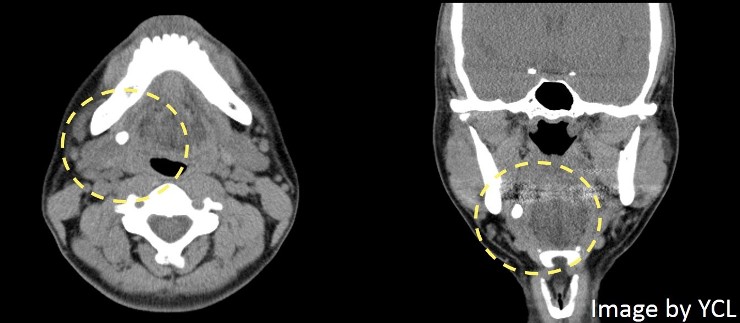

電腦斷層掃描:高解析度的斷層掃描是目前大部分醫師用來檢查唾液腺結石的首選工具[10],當只需要檢查是否有唾液腺結石的時候,不需要在接受電腦斷層前注射顯影劑,因為大多數結石就已含有足夠的鈣成分以供顯影。而與一般X光片相比,電腦斷層掃描對結石的檢查靈敏度高了10倍,但是電腦斷層可能就需要注意切面的間隔不能太寬,以確保結石能被檢查到。

| 在電腦斷層影像中,唾液腺結石有清楚的顯影 |